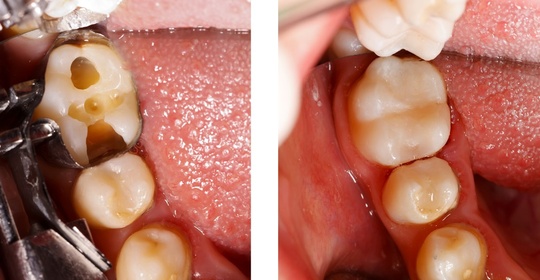

小兒磨牙:小孩牙齒問題的解讀與護理方法!